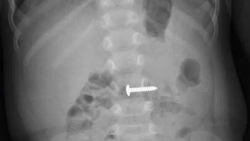

Phẫu thuật thành công cứu cháu bé 34 tháng tuổi nuốt phải đinh vít

Bệnh viện Đa khoa tỉnh Quảng Trị cho biết, các bác sĩ vừa thực hiện nội soi, gắp dị vật là chiếc đinh vít cho bé trai 34 tháng tuổi.